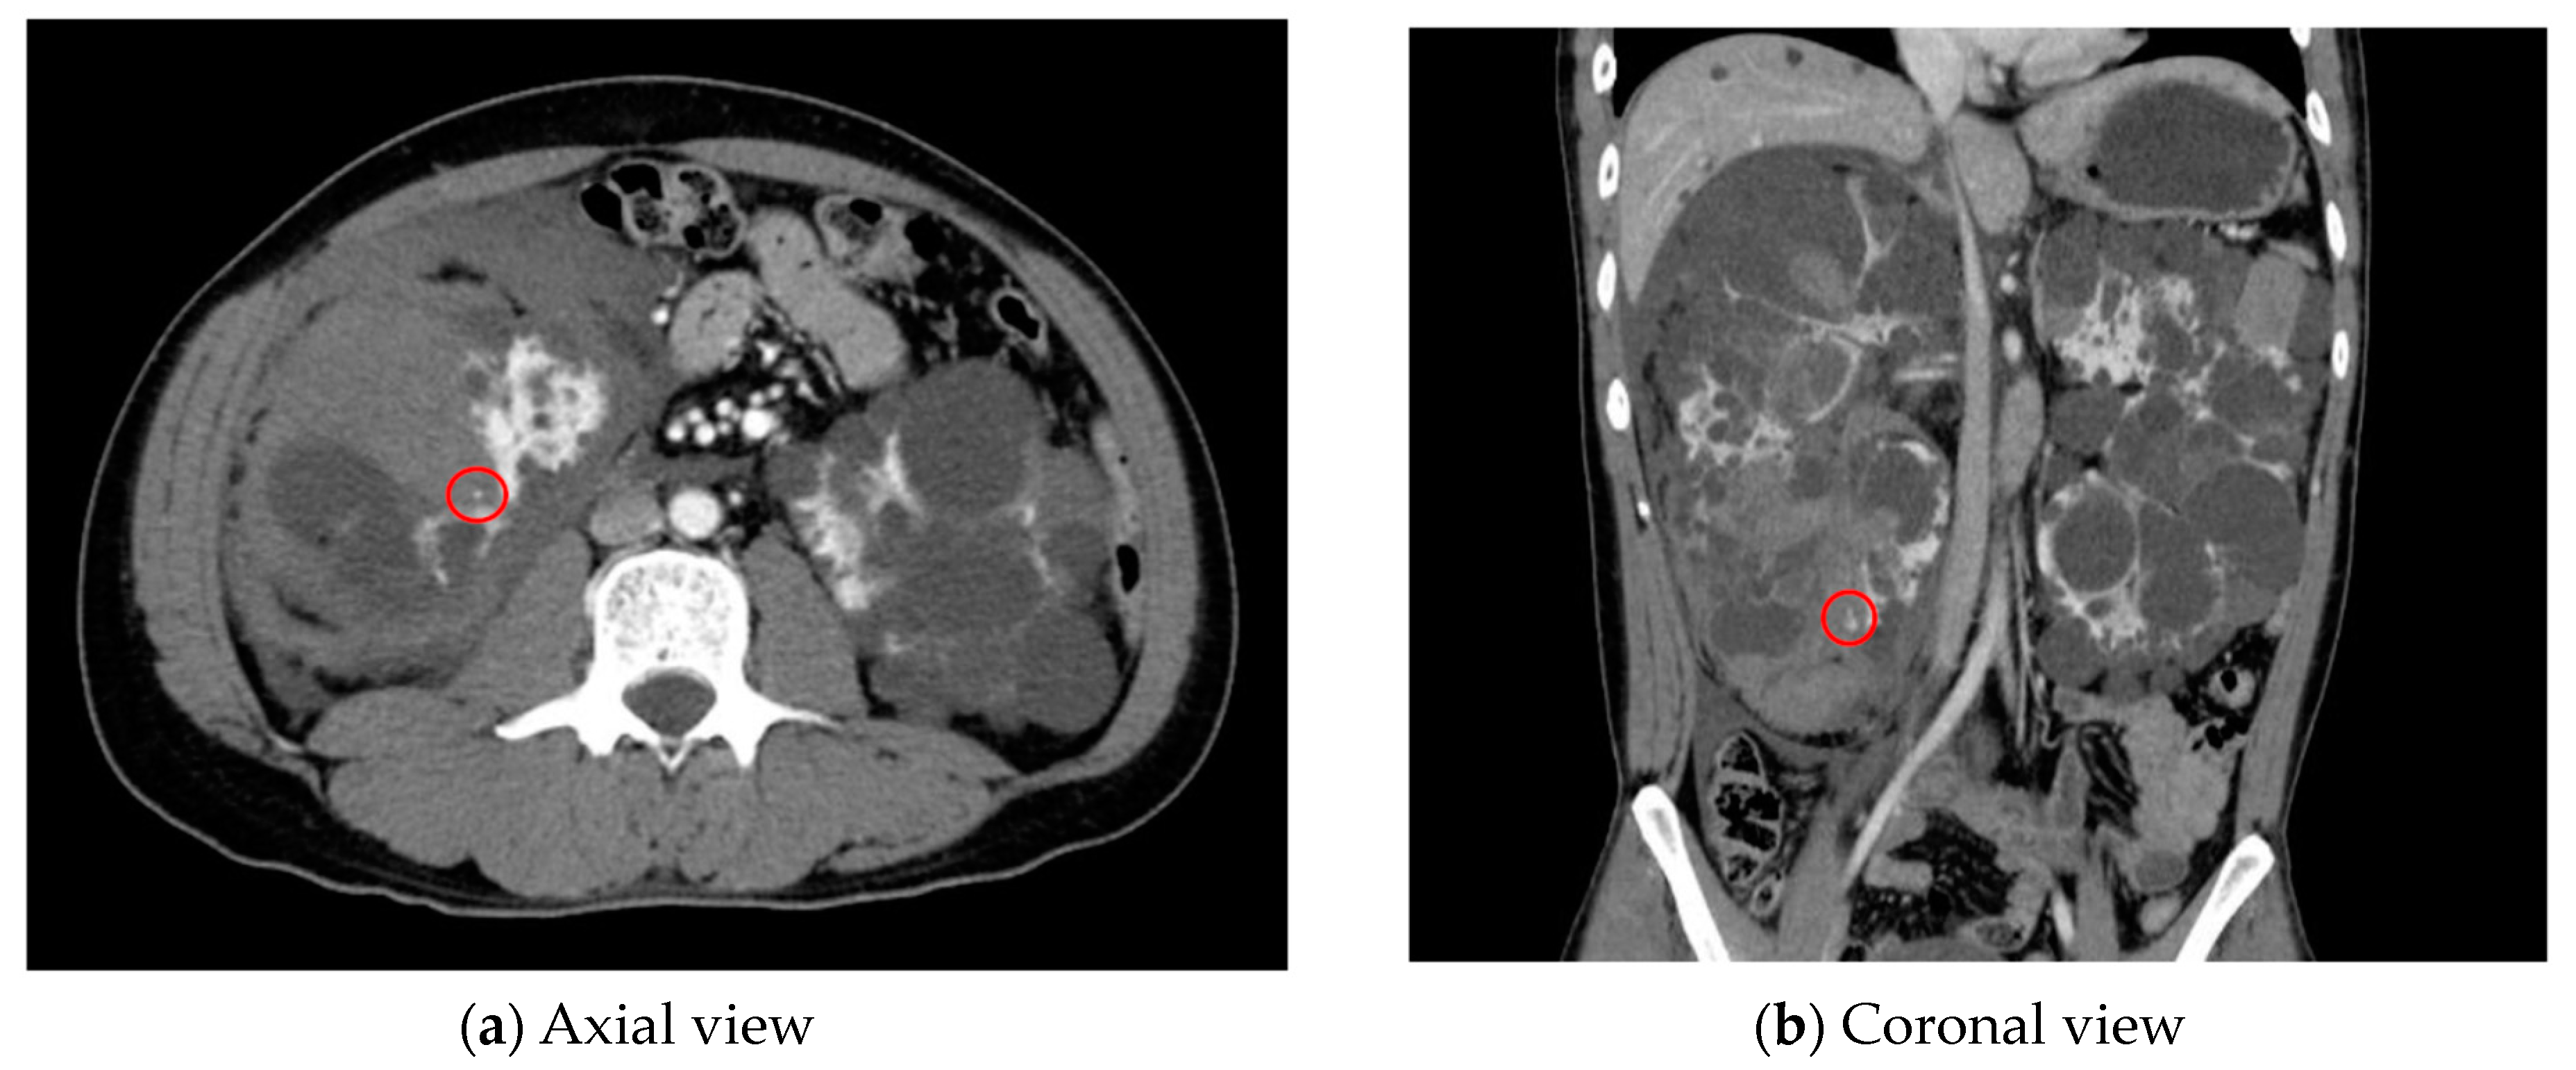

As an example, Figure 1 shows extravasation-induced hemorrhage from a polycystic kidney. Identifying the precise bleeding site on the computed tomography (CT) image presented a challenge. However, upon reviewing the angiography findings, it became evident that the bleeding originated from the area depicted in the CT image. In Figure 2, two instances of extravasation-induced hemorrhage are depicted, marked with the circles. Firstly, (a) displays a pseudoaneurysm visible post-spleen injury. Secondly, (b) illustrates a muscle hematoma in the chest region. In Figure 3, two cases of extravasation-induced hemorrhage are evident. In (a), circles mark extravasation on a fractured pelvic region, indicating a significant injury. Meanwhile, (b) showcases an intragluteal hematoma, highlighting the varied presentations of extravasation across different anatomical contexts. These CT images provide valuable insights into the varied presentations of extravasation cases across different anatomical contexts.

Figure 1.

Extravasation-induced hemorrhage shown in (a,b) with circles from a polycystic kidney.